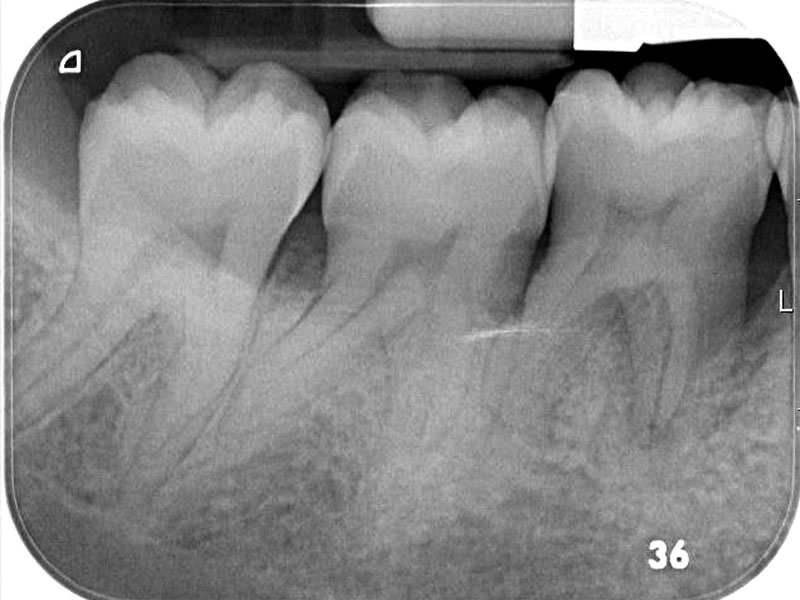

07/08 - 6 months post-operative radiographRegeneration at LR6 with cerabone® and collprotect® membrane using simple papilla preservation technique - Dr. D. Chatzopoulou